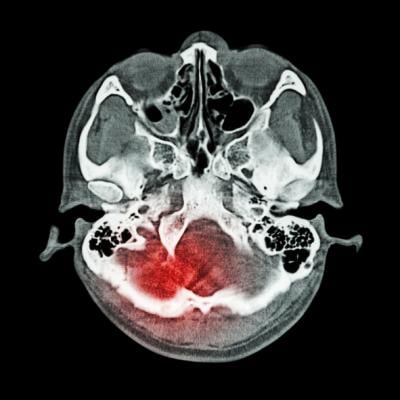

July 21, 2021 — A new study published in JAMA Neurology suggests that certain features that appear on computed tomography (CT) scans help predict outcomes following mild traumatic brain injury (TBI). Patterns detected on the scans may help guide follow up treatment as well as improve recruitment and research study design for head injury clinical trials.

The researchers identified three distinct sets of patterns on the CT scans, indicating different types of damage after head injury which were associated with various outcomes. The results suggest that contusion (bleeding into brain tissue), subarachnoid hemorrhage (bleeding into the cerebrospinal fluid over the brain), subdural hematoma (bleeding between the brain and the thick covering over the brain), and intraventricular hemorrhage (bleeding into the fluid filled spaces in the center of the brain) were associated with worse outcomes 12 months after injury. Epidural hematoma, which describes bleeding between the skull and outer brain covering known as the dura, was associated with incomplete recovery at two weeks and three months, but was not linked to negative longer-term outcomes.